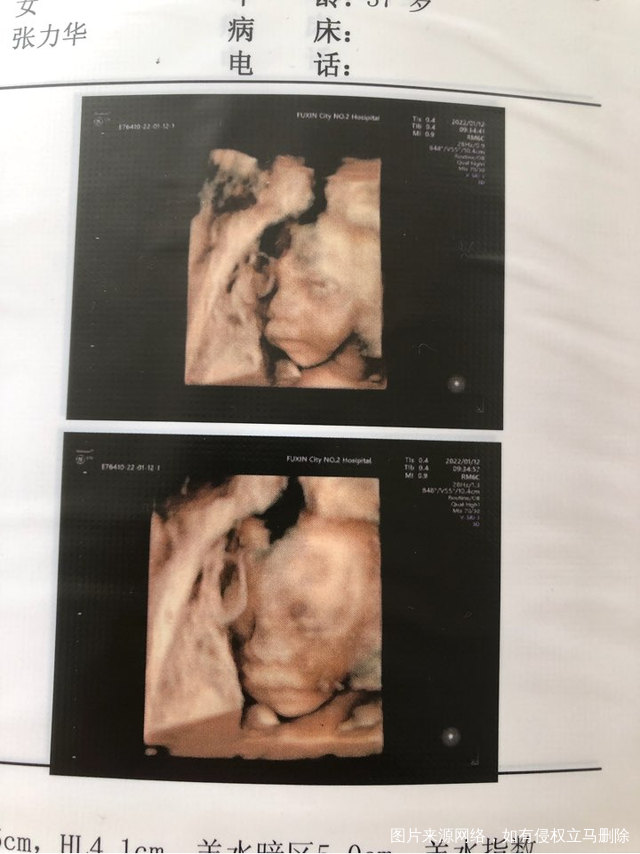

傻丫头

今天做四维一次性通过了。你真棒!不过医生说妈妈太胖了图像不清晰,不过也一次性过了,你真的太给力哈哈。显示你绕颈一周希望你自己别那么贪玩慢慢绕回来哦,比实际周数小一周,妈妈会努力吃有营养的东西,咱们一起加油